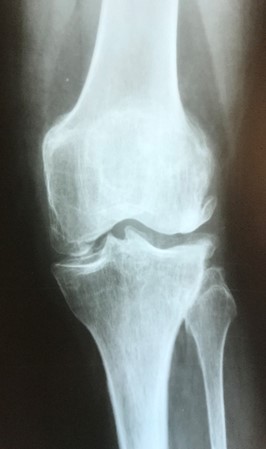

Приклад 3. Хвора К. 52 років. Діагноз: Деформівний IVст. гонартроз, стан після ТЕП лівого КС (2013р.). ІМТ хворої складає 35 балів. Асептична нестабільність компонентів ендопротеза лівого колінного суглоба, міграція великогомілкового компоненту (2017 р.) (рис. 2 а). Хворій виконано ревізійне ендопротезування: видалення компонентів ендопротезу, виявлений дефект медіального виростку великогомілкової кістки тип Т3А за класифікацією АОRI [G.A. Engh, C.H. Rorabeck, 1997]. Під час операції виконана кісткова пластика дефекту. Використаний ендопротез колінного суглоба з подовжувачами.